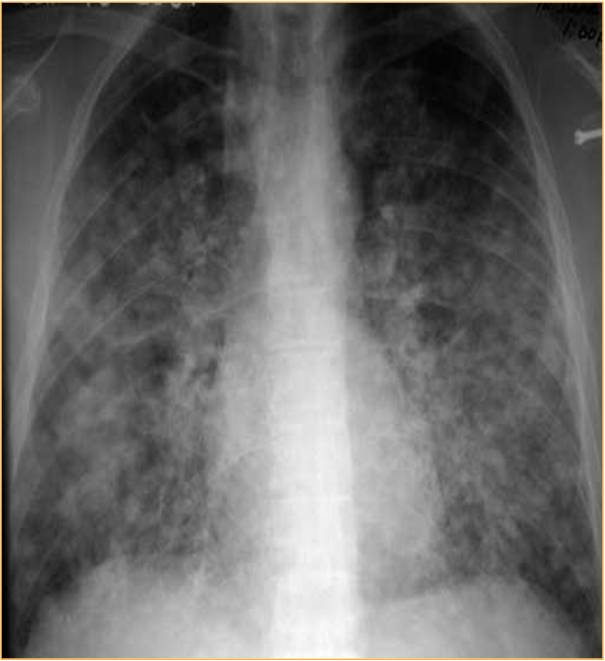

Rx histoplasmosis.jpg